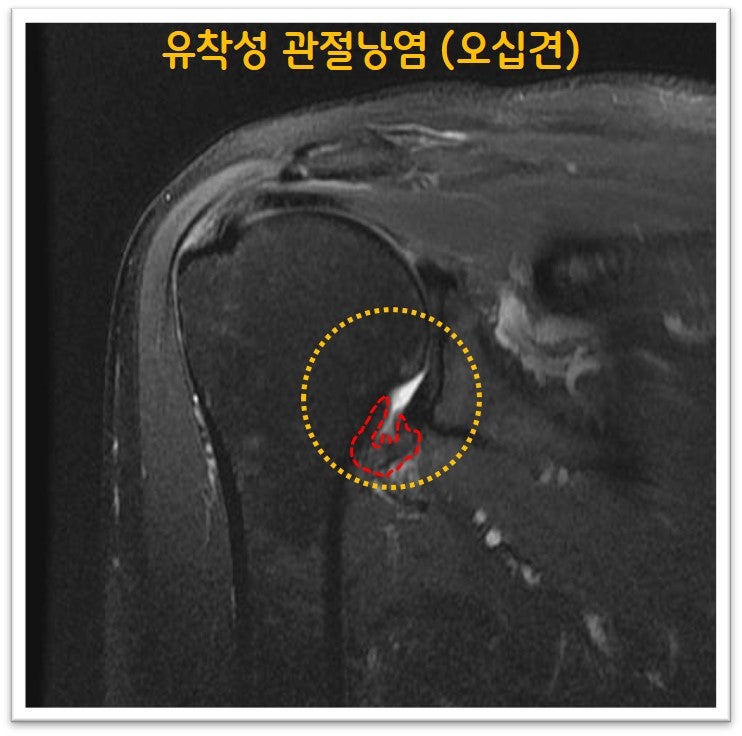

오십견은 의학적 명칭으로 유착성 관절낭염이라 합니다. 즉 관절낭에 염증이 생기면서 유착이 발생되어 통증이 생기고 가동범위 제한이 생기는 것입니다. 치료를 제대로 하지 않을 경우 가동범위 제한이 풀리지 않으며 통증이 지속되고 일상생활에 지장이 있을 만큼 증상을 유발하게 됩니다. 물론 처음부터 시술을 하지는 않으나 적절한 주사치료 및 재활을 했음에도 증상 호전이 되지 않을 때는 뉴핌스 치료 (관절낭유착박리술) 를 통해 탁월한 효과를 볼 수 있습니다. 오십견으로 오랜 기간 동안 고통을 받으시는 분들에게 탁월한 효과와 병의 치료를 할 수 있습니다.